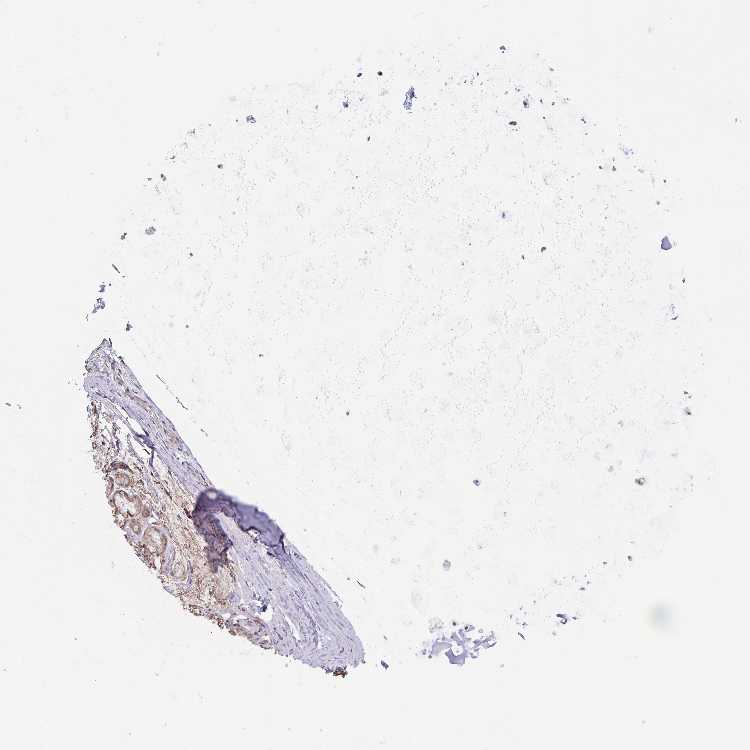

SOFT TISSUE 1 - Antibody stainingi

Antibody staining in the annotated cell types in the current human tissue is reported as not detected, low, medium, or high, based on conventional immunohistochemistry profiling in selected tissues. This score is based on the combination of the staining intensity and fraction of stained cells.

Each image is clickable and will lead to virtual microscopy that enables deeper exploration of all samples and also displays staining intensity scores, fraction scores and subcellular localization as well as patient and tissue information for each sample.

Antibody HPA051846Antibody HPA055785

Chondrocytes -Not detected

Fibroblasts Not detectedLow

Peripheral nerve Not detected-